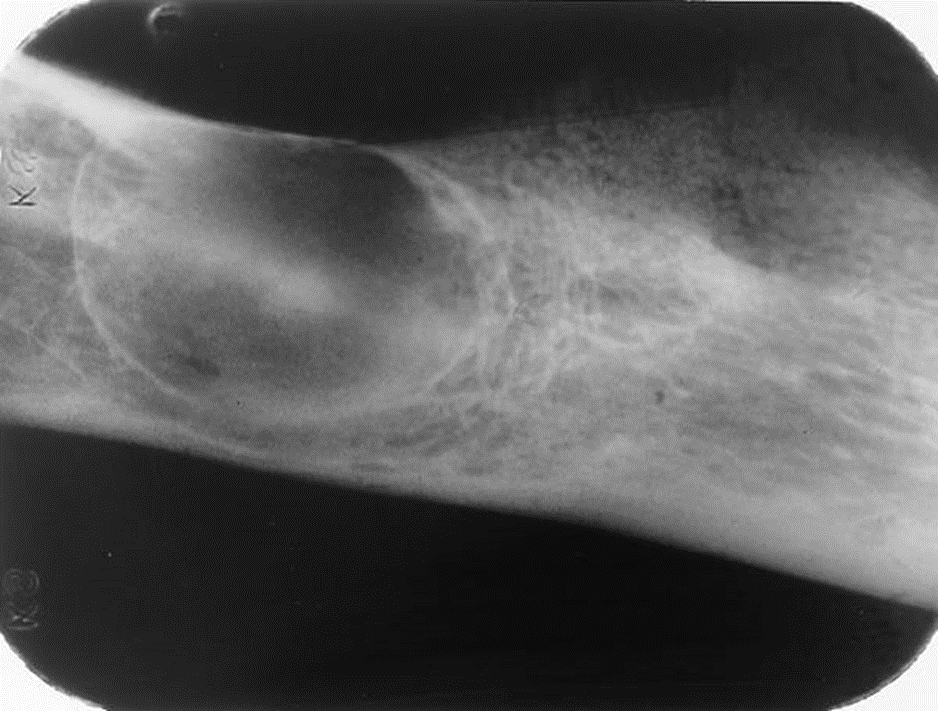

2. Bill is an asymptomatic 47-year-old who presented for routine dental treatment. This radiograph was taken as part of the full mouth survey.

What is your diagnosis?